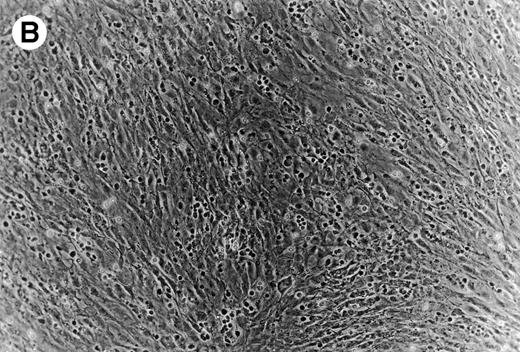

CLL B cells migrate beneath heterologous MSC (Pseudoemperipolesis).

Coculture of CLL cells with the murine-marrow-stroma cell-line, M2-10B4, results in spontaneous migration of CLL cells into the stromal cell layer. This in vitro phenomenon termed pseudoemperipolesis is characterized by the dark appearance of cells that have migrated into the same focal plane as the stromal cells, whereas the more superficial, nonmigrated cells remain refractile (Fig 6).30 Time-course experiments showed that pseudoemperipolesis of CLL cells mostly occurred within the first 2 hours of coculture (Fig 7B). Titration of the input CLL cell numbers showed that concentrations above 1 × 107 cells per 24 well plate did not significantly increase the number of migrated cells (Fig 7C). A 2-hour assay with 1 × 107 input cells was found to be the optimal condition for this assay and hence was used in subsequent inhibition studies. Under these conditions, an average of 7.4% ± 3.7% (mean ± SD) of input CLL cells from 6 different patients migrated into the stromal layer. For comparison, we assessed the migration of Nalm-6 cells and found that 6.9% ± 0.5% (mean ± SE of duplicate tests) of the input cells migrated into the stromal layer under the same experimental conditions.

(A) Representative phase contrast photomicrograph of pseudoemperipolesis of CLL B cells after 2-hour culture on the heterologous murine stromal cell line, M2-10B4. Cells that had not migrated beneath the stromal cells washed off, and the stromal cell layer containing the migrated CLL cells was photographed (200x magnification). Pseudoemperipolesis is characterized by the dark appearance of lymphocytes that have migrated into the same focal plane as the stromal cells. (B) For comparison, this photomicrograph shows reduced pseudoemperipolesis after pretreatment of CLL cells with pertussis toxin.

To establish the role of SDF-1 in the migration of CLL cells into the stromal layer, we used inhibitors that specifically or nonspecifically interfered with the interaction of SDF-1 or CXCR4 on CLL cells. Pertussis toxin was the strongest inhibitor of CLL cell pseudoemperipolesis: only 14% ± 11% (mean ± SD; n = 6) cells compared with untreated control samples (100%) had migrated after 2 hours. Significant inhibition was also observed after SDF-1α pretreatment and addition to the coculture (35% ± 19%; n = 6), and anti-CXCR4 MoAb preincubation of CLL cells (58% ± 16%; n = 6; Fig 8B).